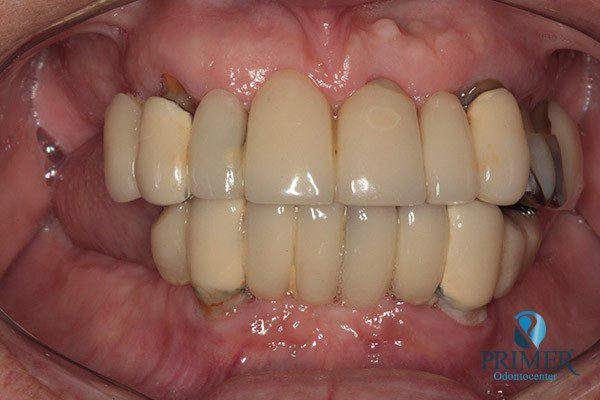

- Depois

- Sorriso final